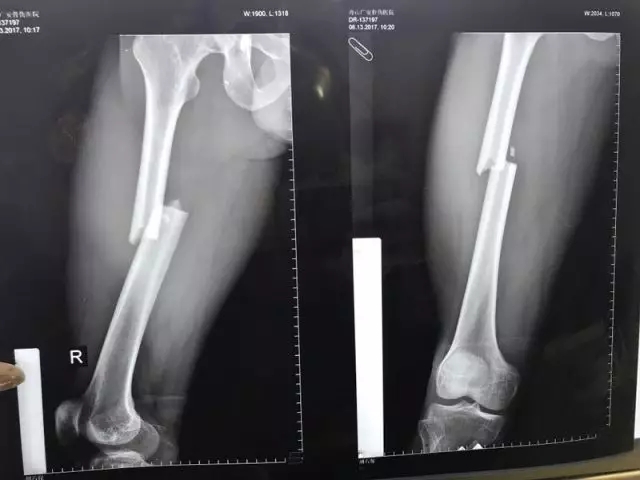

患者入院后進(jìn)行了一系列檢查,發(fā)現(xiàn)股骨干處的粉碎性骨折塊移位特別明顯,下肢出現(xiàn)了短縮、外展畸形,大腿非常腫脹,內(nèi)出血很多,患者十分痛苦。

▲骨折的完美復(fù)位和內(nèi)固定